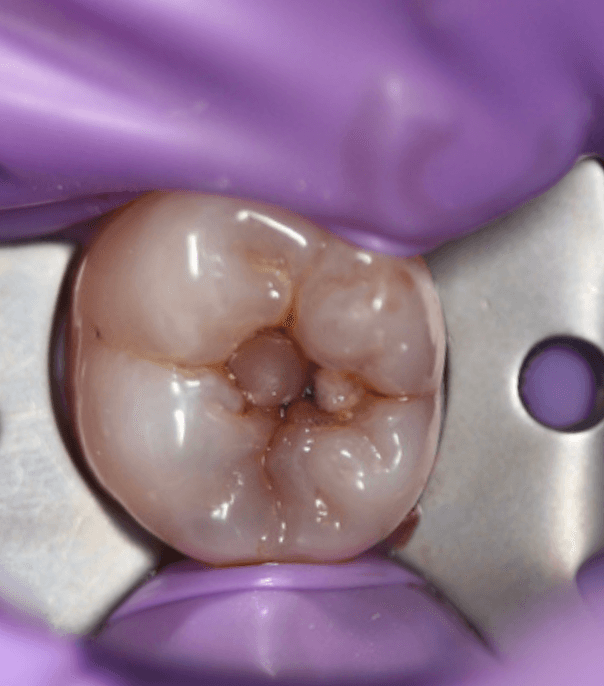

Before Photo